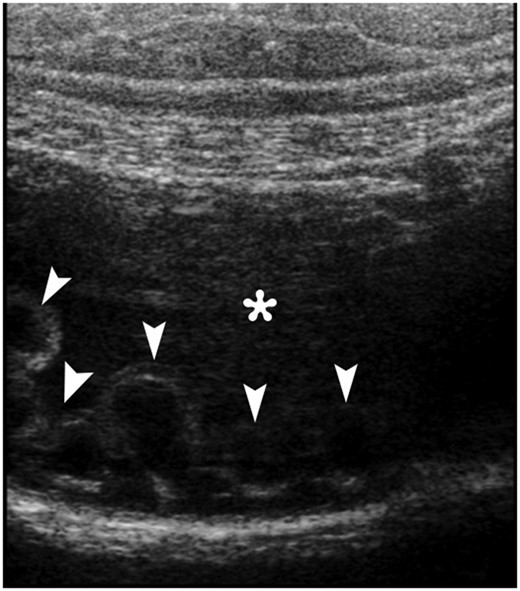

Ultrasonography (USG) revealed multiple anechoic cystic nodularities in the intestinal wall protruding into the fluid-filled lumen (Fig. 1). Because of any diagnose could be done by ultrasound, abdominal computerized tomography (CT) has decided to withdraw.

An abdominal gray-scale ultrasound image obtained with a linear transducer clearly depicts multiple anechoic cystic nodularities (arrowheads) in the intestinal wall protruding the fluid-filled lumen (*).